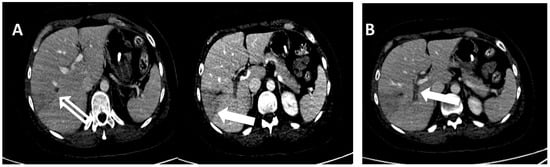

The patient then underwent blood count monitoring. As shown in Table 1, the results revealed the persistence of thrombocytopenia and the presence of normocytic anemia with haptoglobin and bilirubin in the normal range as shown by laboratory data (Table 1). A chest and abdomen CT was therefore performed. The imaging test showed sectorial thrombosis of the right intrahepatic portal branches (VI and VII segment) and a lack of opacification in the left segmental ones, with an associated alteration in perfusion in both the right and left lobe, and some areas constantly hypodense at the level of the aforesaid segments, with a subglissonian location and a predominantly triangular morphology, probably of ischemic significance. Thrombosis of the hepatic veins or the inferior caval vein is not evident (Figure 3).

Figure 3. Thrombosis of the right segmental branch of the portal vein is associated with partial thrombosis of the related branch of the ipsilateral hepatic vein (empty arrow) panel (A). An area of parenchymal hypoperfusion involving V and VIII segments is seen (full arrow) panel (B).